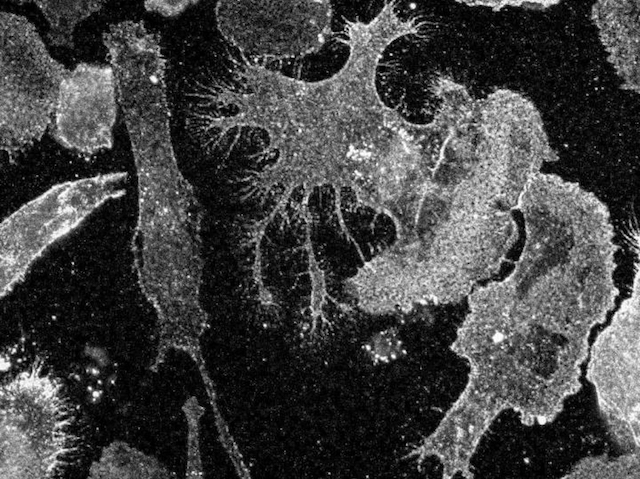

Intergalactic Cell Travel

In one giant leap for cell biology, a SpaceX rocket flew a shoe-box sized laboratory containing living human brain and immune cells to the International Space Station this summer. The mission aims to understand not only how microgravity affects astronauts’ immune systems, but also how our immune cells play a role in disease back down on Earth. The cells were grown from stem cells taken from the skin of people with Parkinson’s disease or multiple sclerosis. It’s thought that these conditions are partly caused by overactivation of the brain’s immune cells, called microglia (pictured). Up on the Space Station, the microglia are held inside a 'CubeLab', which films how they grow and interact over time. The cells are expected to form small balls that behave like miniature organs. This novel experiment could inform the future development of treatments for neurodegenerative diseases or ways to protect astronauts during long-term flights.